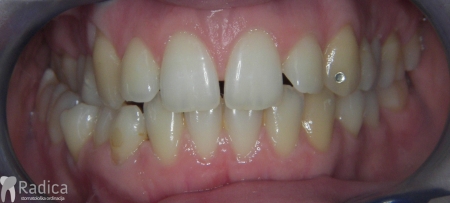

U galeriji slika su prikazani klinički slučajevi ovakvih odraslih pacijenta bilo da se radi samo o ortodontskoj terapiji ili predprotetskoj ortodonciji.

Na sljedećoj slici se mogu vidjeti početak i kraj ortodontske i protetske terapije. Protetske radove radio je dr. Goran Radica.

Na sljedećoj slici mogu se vidjeti početak i kraj ortodontske terapije. Pacijentica je upućena od svog stomatologa nakon što nije bila zadovoljna izgledom osmjeha i odnosom zuba i gingive u privremenom protetskom radu. Napravljena je ortodontska terapija samo u gornjoj čeljusti a nakon toga novi privremeni protetski rad.